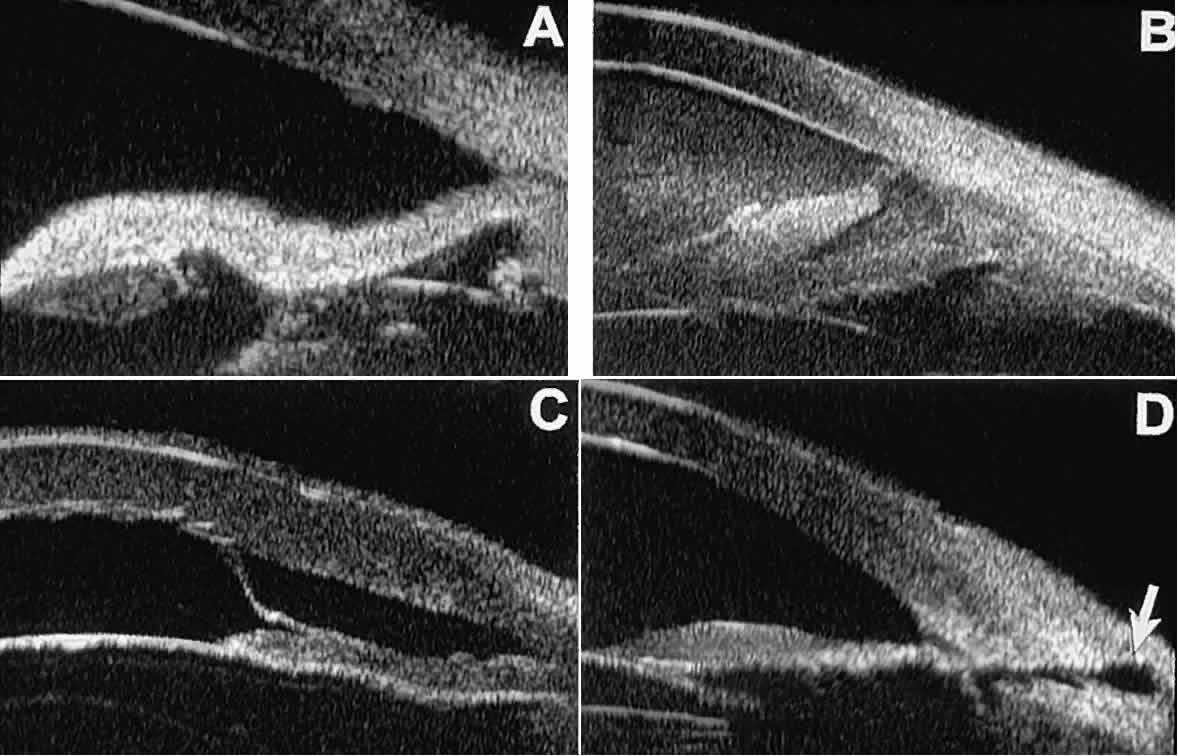

In open-angle glaucoma, UBM can be used to measure the anterior chamber angle in degrees, to assess the configuration of the peripheral iris, and to evaluate the trabecular meshwork (Fig. 9).2,4 The angle configuration can be graded and compared with gonioscopic findings. In certain patients with open-angle glaucoma, UBM can provide information that may be of some diagnostic value (Fig. 10). For example, in pigment dispersion syndrome (see Fig. 10A),6 UBM typically reveals posterior bowing of the peripheral iris (“q” configuration of peripheral iris by Spaeth classification5). In plateau iris syndrome (see Fig. 10B),7 UBM usually reveals abnormally steep anterior angulation of the peripheral iris (“s”configuration of peripheral iris by Spaeth classification5), insertion of the iris from the anterior ciliary body, and retroiridic projection of the ciliary processes. In eyes with peripheral anterior synechiae (see Fig. 10C and D), UBM can reveal the extent of iridocorneal adhesion even if the cornea is hazy or opaque.

Fig. 10. UBM features of special glaucoma cases. A. Pigment dispersion syndrome with posterior bowing of peripheral iris (“q” configuration by Spaeth gonioscopic grading system). B. Plateau iris syndrome with origin of iris from anterior surface of ciliary processes behind peripheral iris, slitlike narrowing of peripheral angle, and abrupt transition from steep peripheral iris to flat iris midzone. C. Broad peripheral anterior synechia with posterior bowing of nonadherent iris. D. Peripheral anterior synechia with aqueous-filled slit between site of iridocorneal adhesion and iris root after cataract extraction with implantation of posterior-chamber IOL.

In eyes with a narrow angle, UBM shows the extent of angle closure, reveals the depth of the anterior and posterior chambers, and identifies pathologic processes pushing the lens and iris forward (Fig. 11).2–4,8 UBM has been able to differentiate between primary angle closure (i.e., cases of angle closure without additional pathology responsible for the anterior lens-iris displacement [see Fig. 11A] and secondary angle closure due to processes such as lens swelling and dislocation (see Fig. 11B), massive hemorrhagic retinal detachment pushing the lens and iris anteriorly (see Fig. 11C), and multiple neuroepithelial cysts of the iridociliary sulcus (see Fig. 11D).

Fig. 11. Angle configuration in eyes with angle-closure glaucoma. A. Primary angle-closure glaucoma with anterior displacement of lens and iris. B. Angle closure secondary to swollen, cataractous lens (phakomorphic angle closure). C. Angle closure secondary to massive hemorrhagic retinal detachment; the subretinal blood is evident in the lower right corner of the photograph. D. Angle closure secondary to multiple peripheral iris cysts.